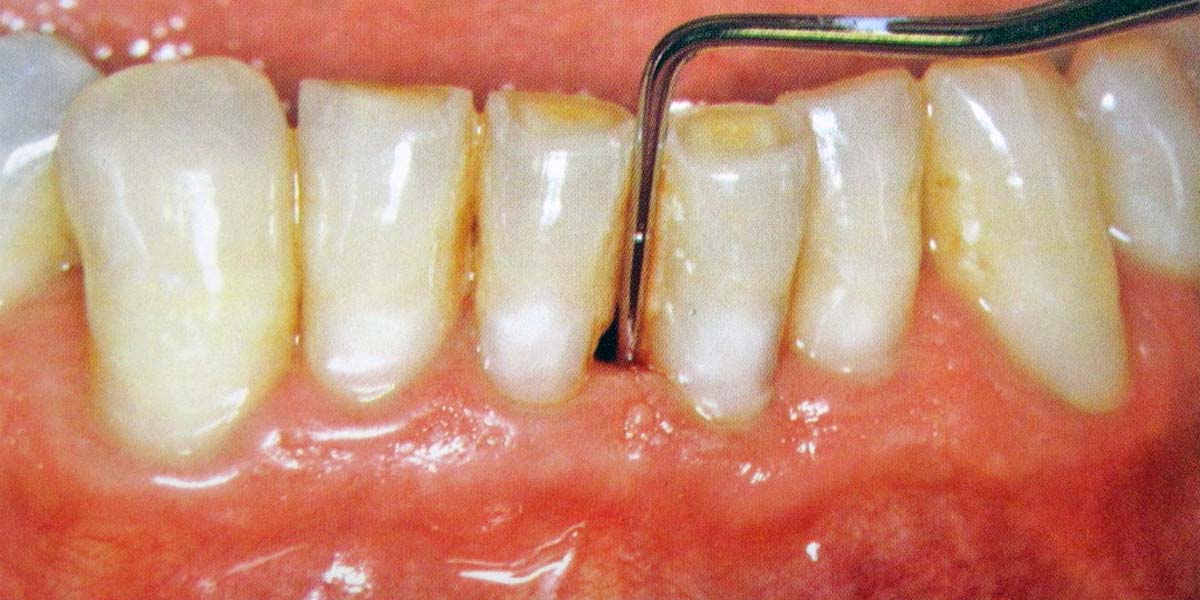

Milyen problémák lehetnek a fogászati implantátumokkal? A fogászati implantátum évtizedek óta a legígéretesebb, a természeteshez leginkább hasonló, megjelenésben és funkcionalitásban tökéletes fogpótlás, rendkívüli életminőség javító előnyökkel. Mivel a fogászati implantátum a természetes foggyökérhez hasonlóan a fog- vagy az állcsontba van beültetve, annak mintegy részévé válik. Így képes arra, hogy nagy